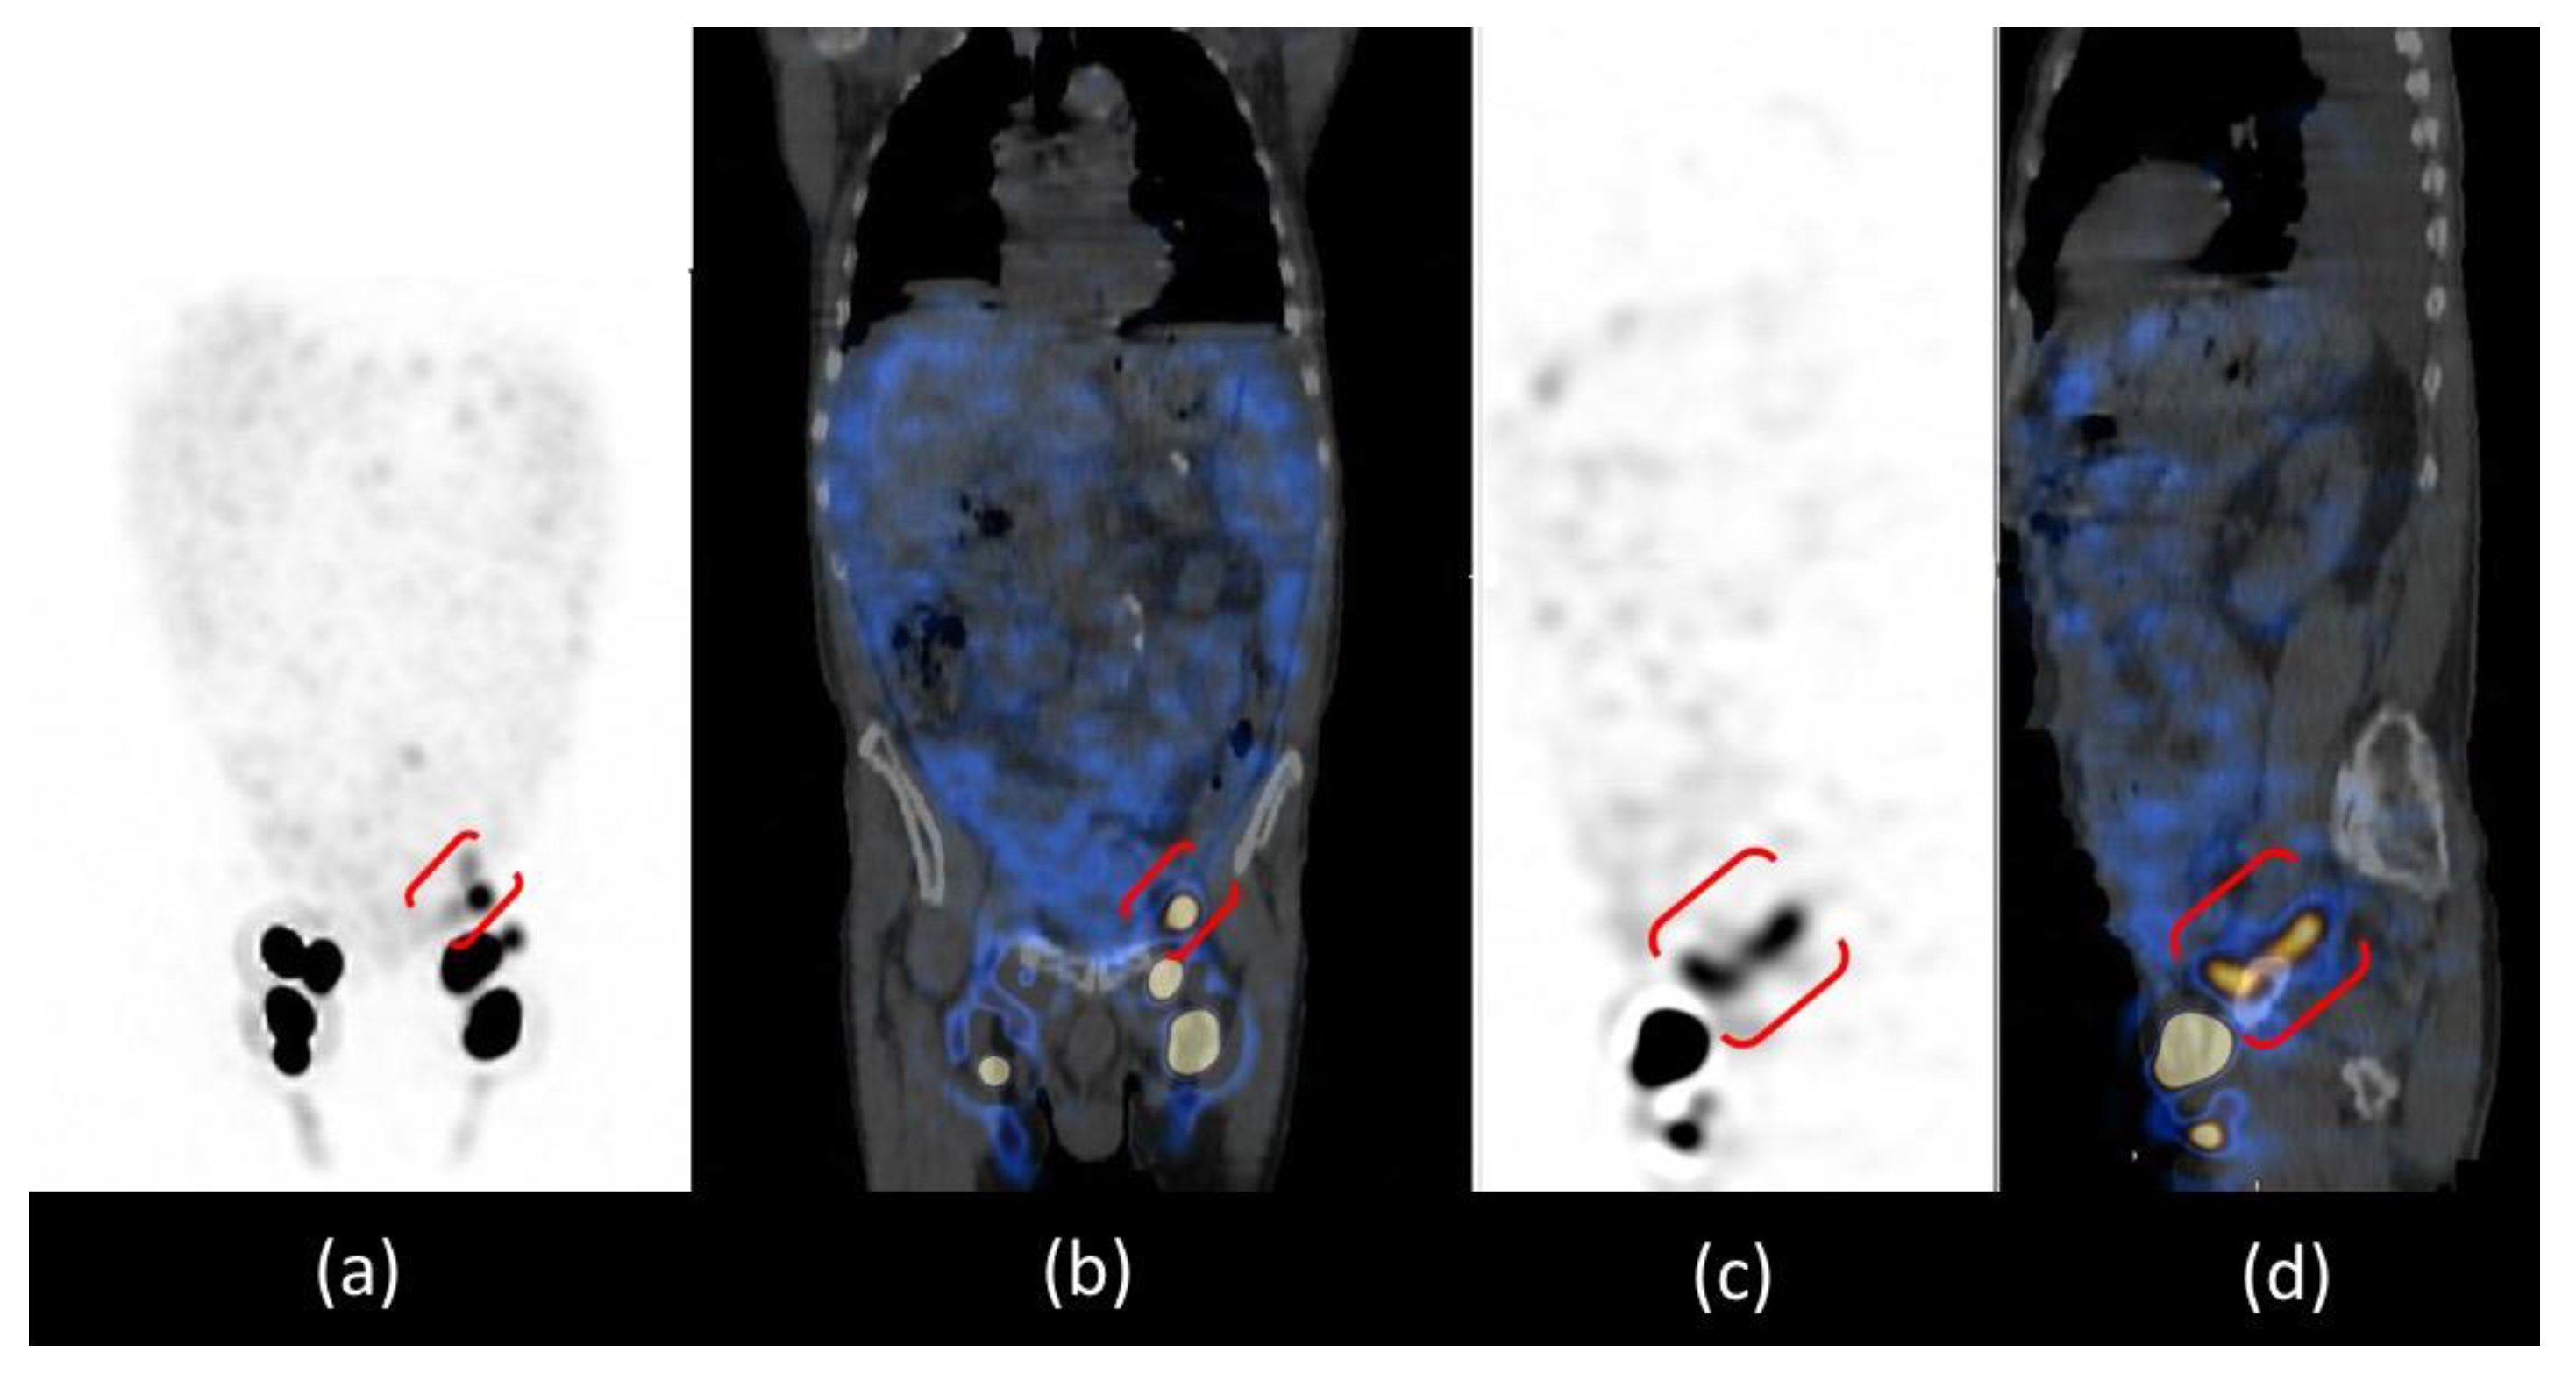

Abdominal SPECT/CT images confirmed the radioactive spot in the left iliac region and the diffuse abnormal accumulation of radiotracer in the peritoneum more intense in the left iliac fossa; the CT co-registration images showed that there was no internal iliac lymph node in that site but a dilatation of the lymphatic pathway at the site of surgical interruption, surrounded by a greater intensity of radioactivity in the ascitic effusion. The cause of chylous ascites was then identified as a consequence of the exudation of chyle through the lymphatic dilatation into the peritoneal cavity (Figure 4).

Figure 4.

SPET/CT whole body lymphoscintigraphy: MIP (a), coronal fused image (b), sagittal SPET (c) and fused images (d). All images confirmed the presence of inguinal lymph nodes and the focal spot of radiotracer uptake in the left iliac region, which in sagittal images is better evidenced as a “whisker” due to the dilatation of the lymphatic pathway at the site of the surgical interruption (red brackets).

For the study of lymphatic vessels, lympho-SPECT/CT moved from an ancillary role to being fundamental due to the high accuracy in detecting even minor lesions and the possibility of correlating them anatomically. Our patient is an exemplary case because lympho-SPECT/CT was decisive in characterizing the spot in the iliac area not as a lymph node but as a lymphatic dilatation and in describing the proximal greater peritoneal accumulation of radioactivity.

Images provided by lympho-SPECT/CT then allowed us to identify the CA aetiology in the exudation of chyle through the lymphatic dilatation identified, which is one of the three possible causes of postsurgical CA [1].